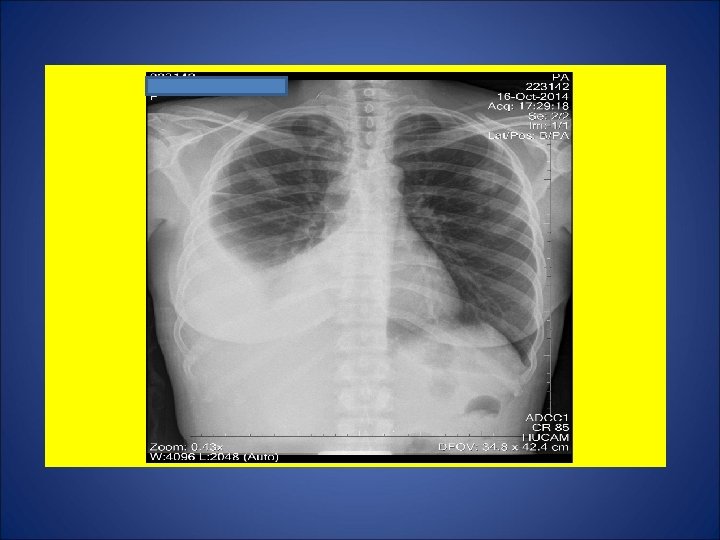

CASO 2, feminina, 37 anos de idade, auxiliar de serviços gerais, natural de Governador Valadares, residente em Cariacica (ES). Por volta de 04 Out 14, procurou P. A. devido a tosse não produtiva, febre, sudorese, calafrios, cefaléia e diarréia há 2 semanas. Foram prescritos algumas medicações (incluido antimicrobiano). Relatou perda de 4 Kg e hiporexia durante as últimas 3 semanas. Remissão da febre, sudorese e calafrios há 1 semana. Em 11 Out, procurou de novo o P. A. devido à ausência de melhora clínica. Foi internada devido ao diagnóstico de derrame pleural à direita, sendo iniciados ceftriaxone 2 g/dia e oxacilina 1 g E. V. 4/4 h. Em 15 out, foi transferida para a enfermaria de Pneumologia do Hospital Universitário para propedêutica de derrame pleural. Negou Tuberculose prévia. Contato intra-domiciliar (mesma cômodo e mesma cama) durante os últimos 14 anos com seu marido em tratamento para tuberculose pulmonar (5º mês). Tabagista e etilista. Dependência química prévia por 1 ano (maconha, cocaína e crack). HIV negativa. Ex. físico: Estado geral regular, P=61 Kg, Alt=1, 68 m, IMC= 21, 6 Kg/m 2. Propedêutica respiratória compatível com derrame pleural.

ESCARROS INDUZIDOS: 1º) 17/10/14: 1 m. L – MUCÓIDE – 55 min: BAC NEG – CULT em curso 2º) 20/10/14: 10 m. L – SALIVA – 40 min: BAC NEG - CULT em curso 3º) 21/10/14: 6 m. L – SALIVA – 46 min: BAC NEG – CULT em curso 4º) 22/10/14: 11 m. L – SALIVA – 50 min: BAC NEG – CULT em curso 5º) 23/10/14: 10 m. L – MUCÓIDE – 1: 10 min: BAC NEG – TRM: M. tuberculosis DETECTADO – CULT EM CURSO